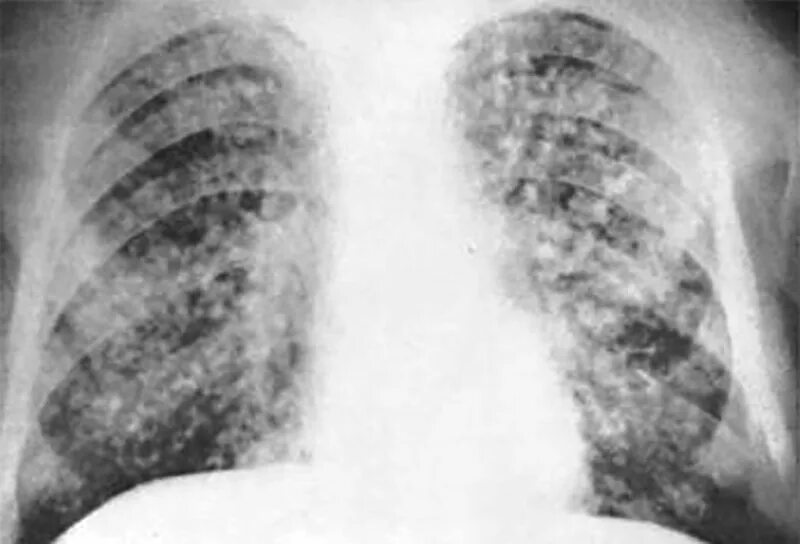

Поражение легких при туберкулезе